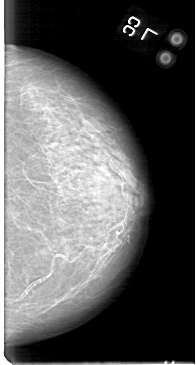

D_4044_1.LEFT_CC

LEFT_CC LINES 5101 PIXELS_PER_LINE 2731 BITS_PER_PIXEL 12 RESOLUTION 43.5 NON_OVERLAY